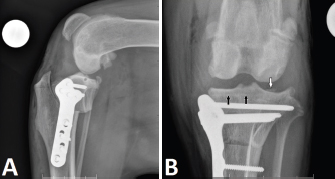

Preoperative radiographs were evaluated and the TPA was measured using a conventional method (Dismukes et al., 2008) by one observer (J.V.J.C.). Postoperative radiographs were evaluated for the location of placement of the proximal jig pins based on the location and trajectory of the radiographically evident pin tract. The shortest distance from the proximal jig pin hole to the osteochondral junction of the tibial plateau on the mediolateral projection radiographs was measured. The pin hole tract was also reviewed on the caudocranial views. Pin placement was considered intra-articular if the pin tract penetrated the osteochondral junction on either radiographic view. The erroneous placement was classified according to the location of the intra-articular jig pin placement as a medial or lateral plateau. Medial plateau intra-articular jig pin placement was defined as a visible radiolucent tract directly over and through the osteochondral junction of the medial tibial plateau in the mediolateral view (Fig. 1A and B). Lateral plateau intra-articular jig pin placement was defined as a radiolucent tract within 3 mm of the medial subchondral bone surface on the mediolateral view (Fig. 2A), and jig pin trajectory penetrating the osteochondral junction of the lateral tibial plateau on the caudocranial view (Fig. 2B). For those dogs that had evidence of intra-articular jig pin placement, details such as age, sex, breed, and weight were recorded.

Fig. 2. Mediolateral (A) and craniocaudal (B) radiographs illustrate lateral tibial intra-articular jig pin hole placement. The black arrows show the pin tract distal to the medial subchondral bone, and the white arrow shows an osteochondral fragment created during intra-articular pin placement.